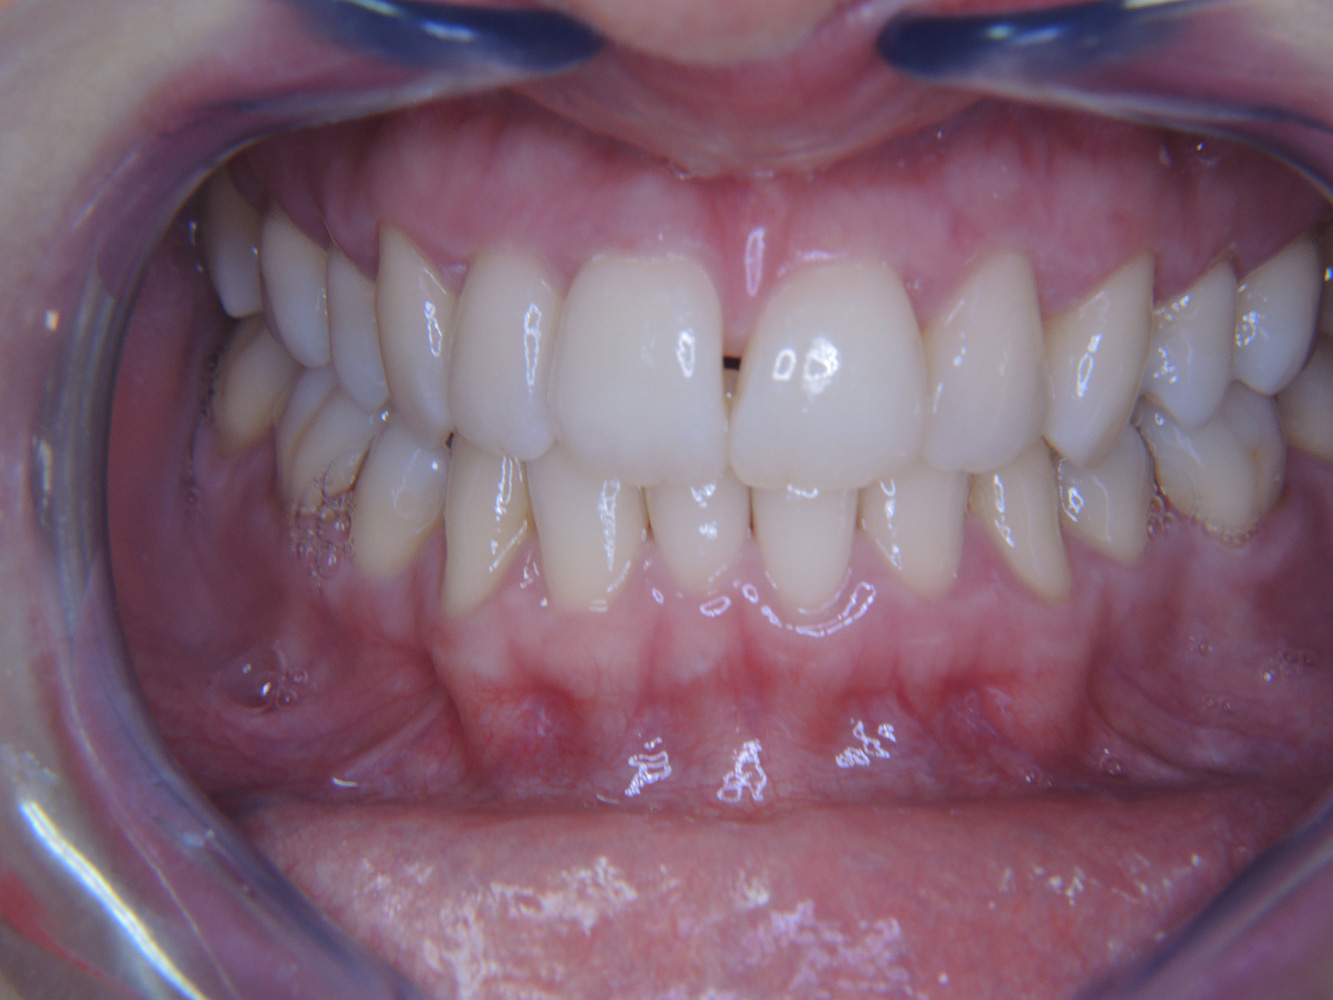

Die gesunde Patientin mit parodontaler Vorerkrankung

Die 68-jährige Patientin hat keine zahnmedizinisch relevanten allgemeingesundheitlichen Vorerkrankungen oder Medikation, auch aus dem Lebensstil ergibt sich kein besonderes Risiko. Die Patientin hat zwei Implantate (3. Quadrant, seit fünf Jahren) sowie eine parodontale Vorerkrankung (Parodontitis Stadium IV, Grad B) mit Zahnverlust. Derzeit zeigen sich stabile parodontale Verhältnisse. Für die Prophylaxesitzung ergeben sich vier Empfehlungen in den Bereichen Anamnese/Befund, Motivation/Instruktion, der Wahl der geeigneten Instrumente und für Resümee/Folgetermin. mehr Infos